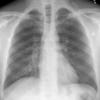

Normal PA Male

Date: 12/06/2014

Views: 6732